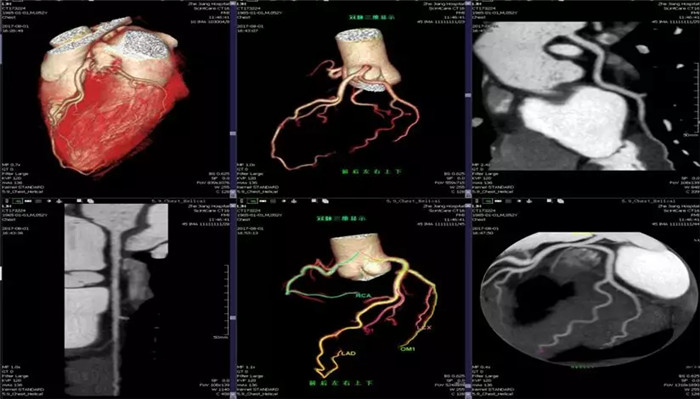

全域精圖

·心臟掃描應用

·全面臨床功能